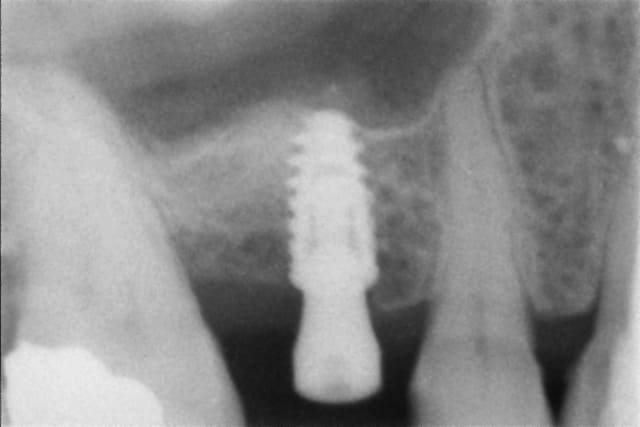

En illustration, j'ajoute des clichés pour RE expliquer pour ceux qu'on pas pigé que c'est opérateur dépendant.

cliché 1 : l'implant mésial a pas été assez enfoui, cratérisation distale (site d'extraction du jour de la pose)

cliché 2 : le pilier de droite est trop bas (pas de 3mm le jour de la pose, mais patient voulait une pro : mis un 1,5 angulé...bof). Sanction : ça commence à chier en mésial.

cliché 3 : enfouissement ok : quand c'est posé comme ça avec la bonne vis qui arrive à la bonne hauteur pour la prothèse définitive, on a JAMAIS de souci de "cratère"

cliché 4 : EII sur une 36, l'os a l'air de quand même bien aimer ce col quand la prothèse est à distance...

Moralité : c'est la prothèse qui dicte l'enfouissement, et pas le niveau osseux dispo. Mais ptêt que certains font autrement, après faut pas chercher pourquoi on cratérise : l'espace biologique.